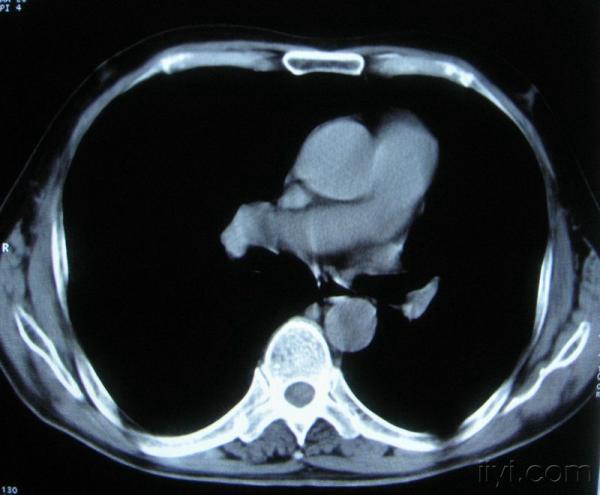

男。60岁,胸片示支气管炎治疗后复查CT。

你指那个肯定是淋巴结,中央系坏死,这很常见,特别在双侧腹股沟会经常看到。这个双侧腋窝及纵隔见多发小淋巴结征。

根据位置考虑应该是淋巴结,密度不均,是因为肿大的淋巴结中心液化坏死